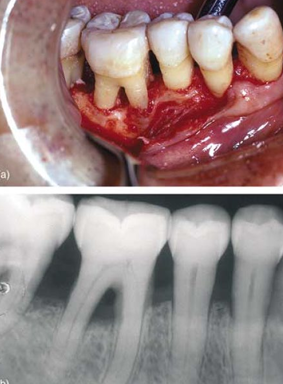

restorative contributing factors

-overhanging restorations

-plaque retentive

margin location

-inflammation and/or uncontrolled bone loss if restorations impinge on biologic width